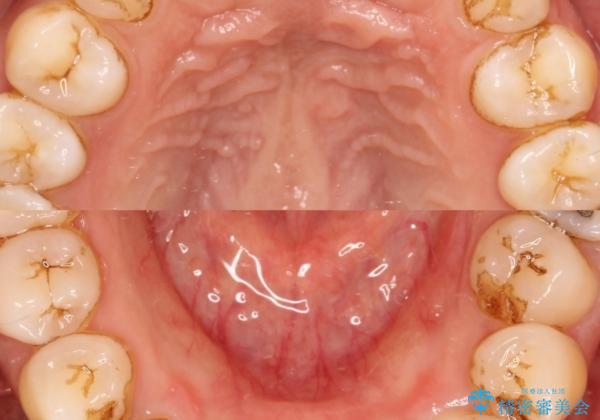

歯科衛生士による、歯石や着色除去の前後写真です。

- 毎日の喫煙による着色を気にして来院されました。前歯から奥歯まで広い範囲で着色が認められたため、歯科衛生士による専門的な機械を使用したPMTC(自費クリーニング)を行いました。